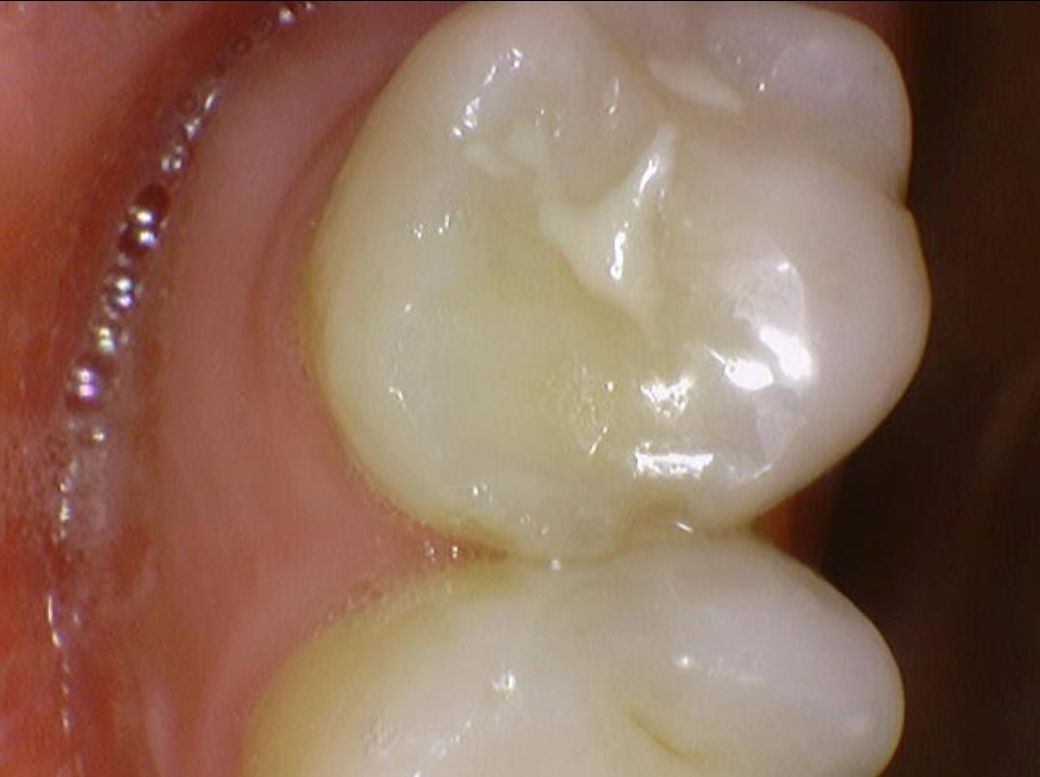

여쭙고 싶은건 깨진건(이 일부가 떨어져나감) 저도 보이기는 하는데

이게 시간이 지날수록 발치가 이어질 안좋은 크랙인지, 아니면 일단 10년 정도는 조심스럽게 그냥 살아도 괜찮은, 흔한 경우인지 입니다

밑에 구강내부 사진(16,17,26,27번 치아)들에서

치료가 반드시 필요한 치아는 몇번째 사진 이런식으로 설명 부탁드립니다

두번째가 깨진 부분들 다 인접면 충치라고 그러던데 다른치과에서 찍은 교익 방사선,파노라마,사진들 모두(각자 다른 치과) 고려했을때 법랑질 뚫고 간 흔적이 안보여서 판독 부탁드리려고 합니다

정말로 인접면 충치인지요..

• 1번 째 사진

• 2번 째 사진

파절된 부위가 보이긴 합니다 하지만 금이 깊게 진행될 정도로 보이는 것은 아닌 것으로 판단이 됩니다 정확한 확인은 직접 확인을 해 봐야 알 수 있습니다.

예전에 치아 사이에 레진치료를 한곳이 떨어진 부분이 몇군데 잇는거 같습니다. 작은 사진을 찍어보시고 치료를 받으시는게 좋을것같습니다.

3. 사진상으로 추가적으로 확인해봐야할 치아는 #16, #25, #26, #36, #46 입니다